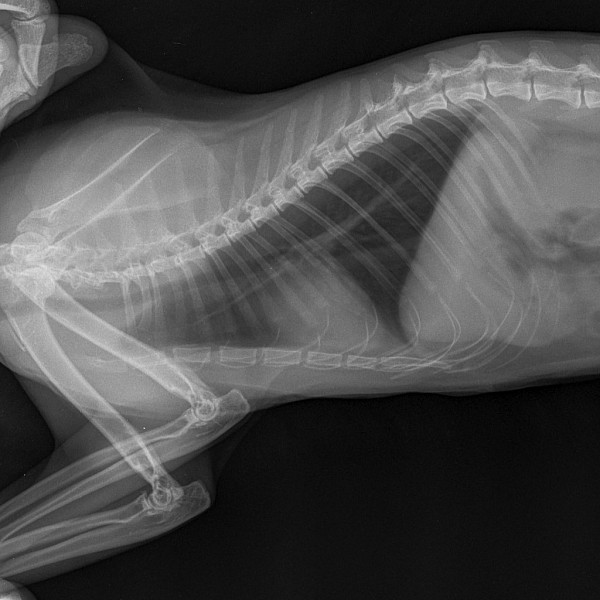

Рентгеновские снимки головы кошки в боковой проекции